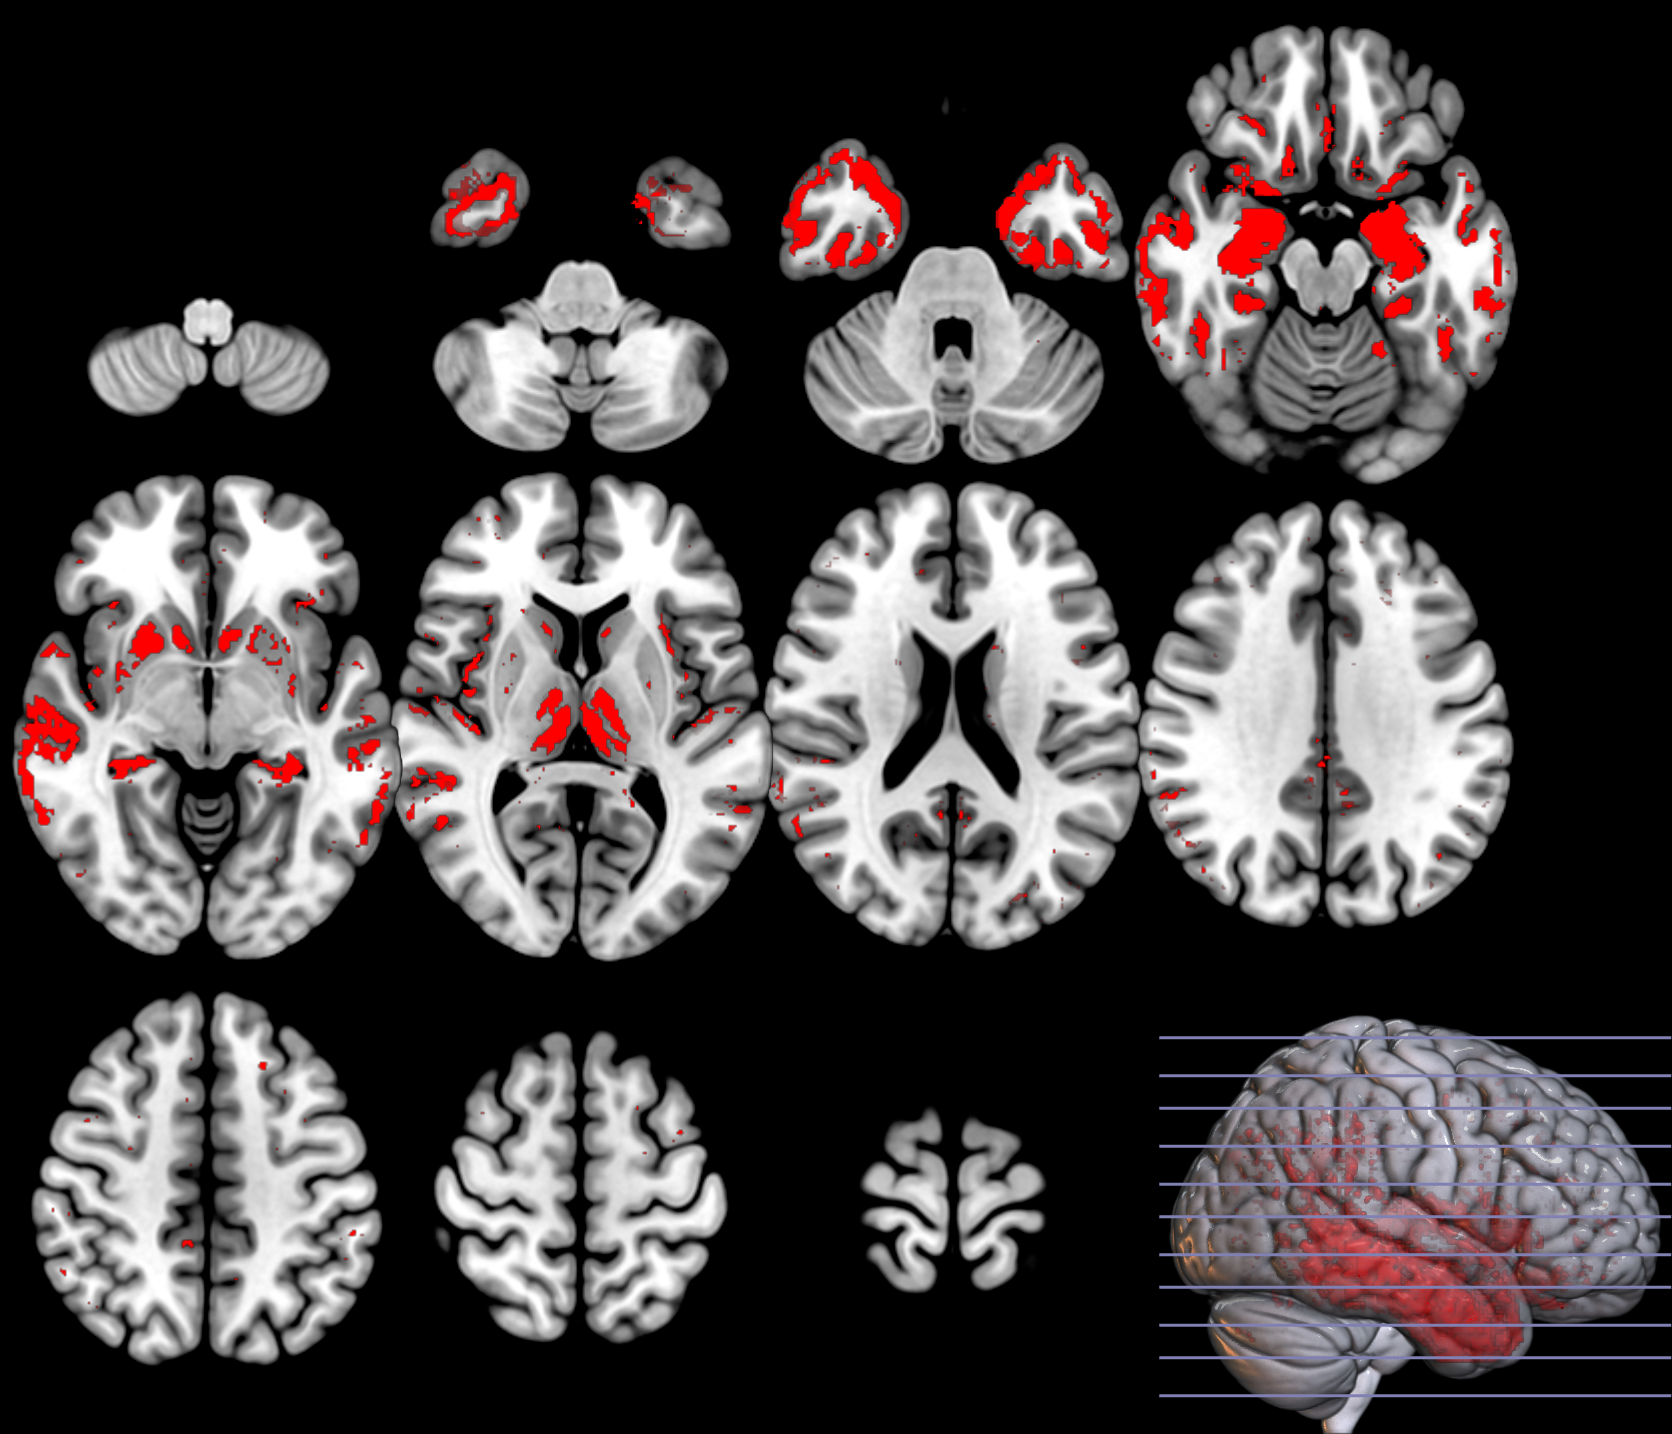

Following the aforementioned methods, we fit the set of parameters using linear SVM and evaluate the statistic on the original set (see figure 11). As shown from this figure the resubstitution estimate provides a more optimistic value in the Acc distribution than the -fold based estimate. Note that this analysis is independent of the selected fold as we are performing folds, one per voxel. However, both are optimistic since the mean of the distribution is not clearly distributed around (it is already shifted to the right, beyond the effect due to real significant regions). The effect is even larger when the dataset is slightly imbalanced, the case of over-powered datasets, as shown in the bottom of the latter figure (using 228vs188). On the contrary, note how the correction based on the bound derived in [13] clearly shifts the obtained by resubstitution to the left, resulting in a better (conservative) estimation of the statistic in the whole volume.

Based on the and values from the original dataset, and the ones obtained using a permutation analysis () for a selection of structures, e.g. hippocampus, we can compare the SPM with the previous inference approaches, as described in section 2.2.3. Note that in this paper the huge amount of voxels contained within an image limits the permutation analysis in this sense to some specific structures. Results on the hipocampus are depicted in figure 13. The permutation analysis reveals how the power of the approach is affected in this featured region, where a real effect might be found in almost the whole structure. The statistical power of the is preserved through the permutation procedure ( detected voxels vs voxels as shown in the same figure). It is also worth mentioning the CDF of the errors derived in the specific region and the distribution of the p-values within it. Recall that the dataset include advanced AD subjects thus the selected structure should be clearly affected by the disease.

To preliminary extend the analysis to the whole volume we approximately simulate the null distribution outside this featured region in two steps. First, we compute the set of p-values in the hippocampus (around voxels) following equation 16 and determine the T threshold that approximately provides the significance level, e.g. . Then, assuming that for any the probability of observation is , we threshold the rest of the image to obtain the significant voxels showing an effect. This approach clearly needs the multiple-comparison correction as several dependent or independent statistical tests are being performed simultaneously at the given significance level. Therefore, we decrease the significance level down to to avoid the presence of false positives in permutation analyses and then compare with SPM in the whole volume using the aforementioned configurations. In figure 13 we show the detection ability together with the control of type I error in the approach (map in red font). Note how the permutation test affects the detection ability of the classical CV approach (map in green font) and how the uncorrected voxelwise SPM approaches (in blue font ) tends to inflate false positives.